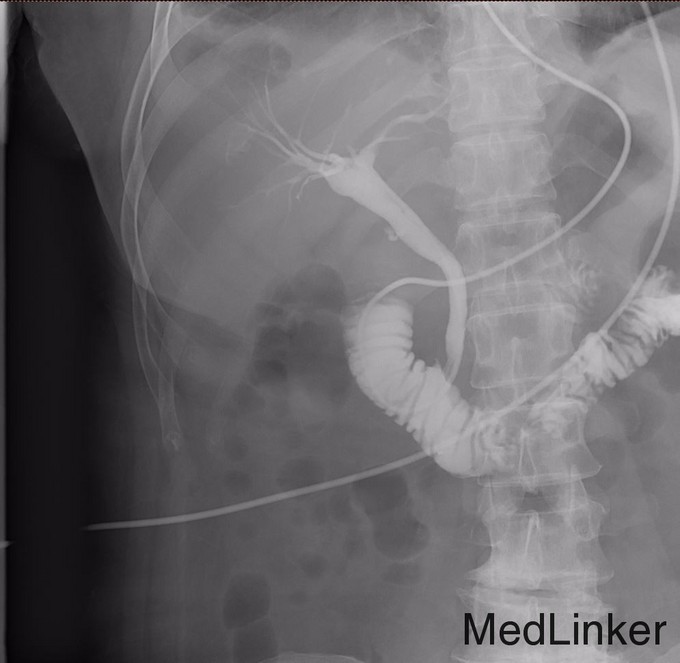

诊断: 胆囊结石 胆总管结石 胆源性胰腺炎 治疗:胃肠减压,抗炎,补液,抑酶,抑酸治疗,急诊内镜至十二指肠,见十二指肠乳头肿胀,选择性胆管插管顺利,造影见胆总管直径12mm,末段可见数处充盈缺损,最大大小约6mm,行乳头肌切开(EPT),以12mm球囊扩张乳头(1ATM,40s)后,取石球囊取出黄色结石1枚及少许泥沙样结石,球囊及盐水清理胆道,再次造影见胆总管内无充盈缺损,留置鼻胆引流管,选择性胰管插管顺利,留置5Fr5cm胰管塑料支架一枚。次日,患者血淀粉酶恢复正常,血脂肪酶降至156U/L,腹痛明显缓解。EPT第二日,全麻下腹腔镜胆囊切除术(LC),手术顺利,术中发现胰腺无坏死,未处理胰腺,LC术后2天再次经EPT留置的ENBD管造影,未发现胆总管结石,复查血淀粉酶及脂肪酶,均恢复正常,拔管出院。